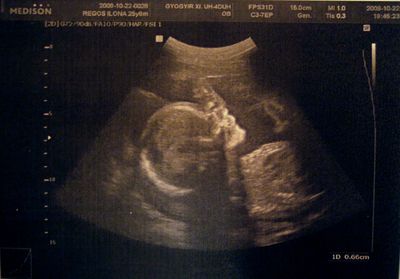

Akkor a 20 hetes pocakok.

19+5

20+0